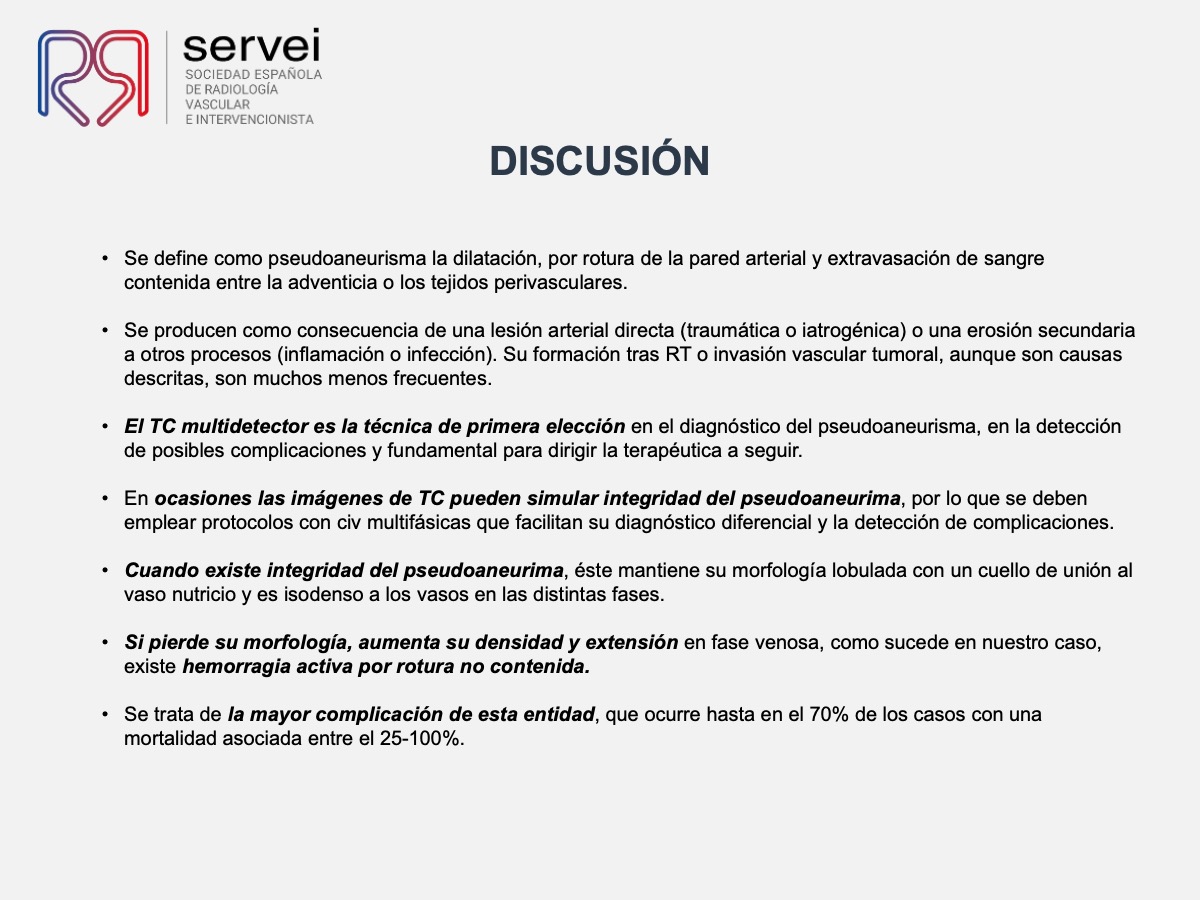

- Pseudoaneurisma arteria obturatriz-rectorragia 01

- Pseudoaneurisma arteria obturatriz-rectorragia 02

- Pseudoaneurisma arteria obturatriz-rectorragia 03

- Pseudoaneurisma arteria obturatriz-rectorragia 04

- Pseudoaneurisma arteria obturatriz-rectorragia 05

- Pseudoaneurisma arteria obturatriz-rectorragia 06

- Pseudoaneurisma arteria obturatriz-rectorragia 07

- Pseudoaneurisma arteria obturatriz-rectorragia 08

- Pseudoaneurisma arteria obturatriz-rectorragia 09